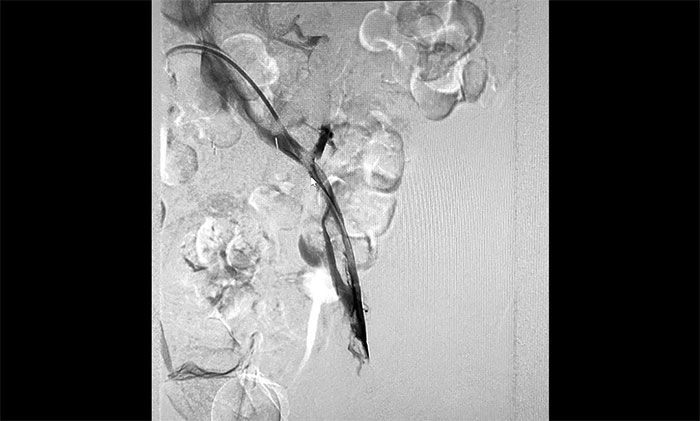

12月15日,席刚明教授在王贵平博士及介入团队协助下顺利行将一个形似伞状的人工滤器经患者右侧股静脉穿刺迅速置入肾静脉下方,“网”住了通往心血管和肺部的致命栓子,阻挡血液栓子进入肺动脉,及时挽救了患者生命。之后对病变血管进行了血栓抽吸术,及接触性溶栓,抽出了大量血栓,复查下肢造影示血栓基本消失,下肢静脉血管再通,整个手术顺利完成。术后,患者下肢肿胀好转。

▲ 下腔静脉滤器顺利置入

▲ 下肢深静脉血栓形式

▲ 下肢静脉血管顺利再通